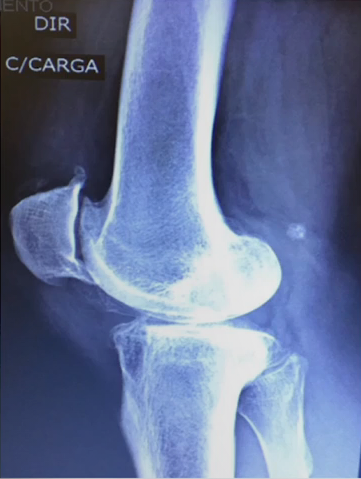

Classificação de Kellgren-Lawrence

Grau 4

Redução do espaço articular acentuada + destruição óssea